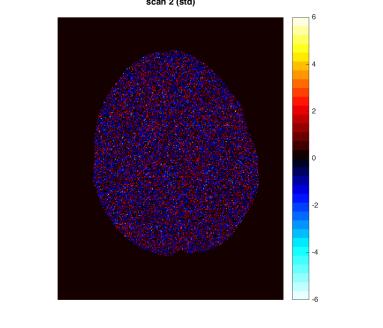

By design, there is a large background change but no change in the lesion. A direct difference between the two scans shows a global non-homogeneous background change while failing to detect changes in the lesion (Figure 1, Row 1 and Column 3). In contrast, the analysis based on the model-based standardized differences proposed in this paper is successful (Figure 1, Row 2 and Column 3). Specifically, the second row shows the standardized scores using the proposed robust EM algorithm RB-SGMM and background adjustment via the soft-assignment transformation . The estimated background parameters are those given in (4.1). The standardized scores show a distribution close to standard normal with little anatomical structure except for the lesion. The standardized difference in the third column again has a distribution close to standard normal and exhibits the lesion change clearly at -6 standard deviations away from 0.